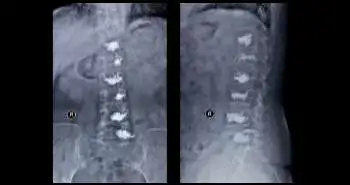

A retrospective cohort study was conducted on 28 patients treated for osteoporosis-related thoracolumbar vertebral body compression fracture between 2011-2015. Treatment involved posterior thoracolumbar fusion or lumbar fusion using CICPS technique. Treatment effectiveness was evaluated using the Oswestry Disability Index scores and visual analog scale (VAS), the degree of fracture reduction, and correction of kyphosis. The safety of CICPS was mainly assessed for intraoperative and postoperative complications. CT-scan, radiography and MRI imaging outcomes were also evaluated.

All 28 patients were having severe osteoporosis. The VAS at final follow-up (0.50 ± 0.69) was significantly lower as compared to before surgery (4.93 ± 1.30). There was a significant decrease in the Oswestry Disability Index score at final follow-up, i.e., from 57.39% ± 14.46% to 6.83% ± 15.38%. It was also observed that at the final follow-up the Radiologic evaluation of vertebral height and Cobb angle showed measurable fracture reduction and satisfactory correction of kyphosis. No occurrence of screw loosening or symptomatic complications were seen, only a few cases presented cement leakage (10.3%; cement leakage most common in AO type A3.3) from CICPS.